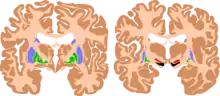

| The basal ganglia are instrumental in motor function. Damage to these areas may results in athetoid/ dyskinetic cerebral palsy (ADCP), or subtle movement disorders. | |

CP in general is a non-progressive, neurological condition that results from brain injury and malformation occurring before cerebral development is complete.[5] ADCP is associated with injury and malformations to the extrapyramidal tracts in the basal ganglia or the cerebellum.[1] Lesions to this region principally arise via hypoxic ischemic brain injury or bilirubin encephalopathy.[1][5]